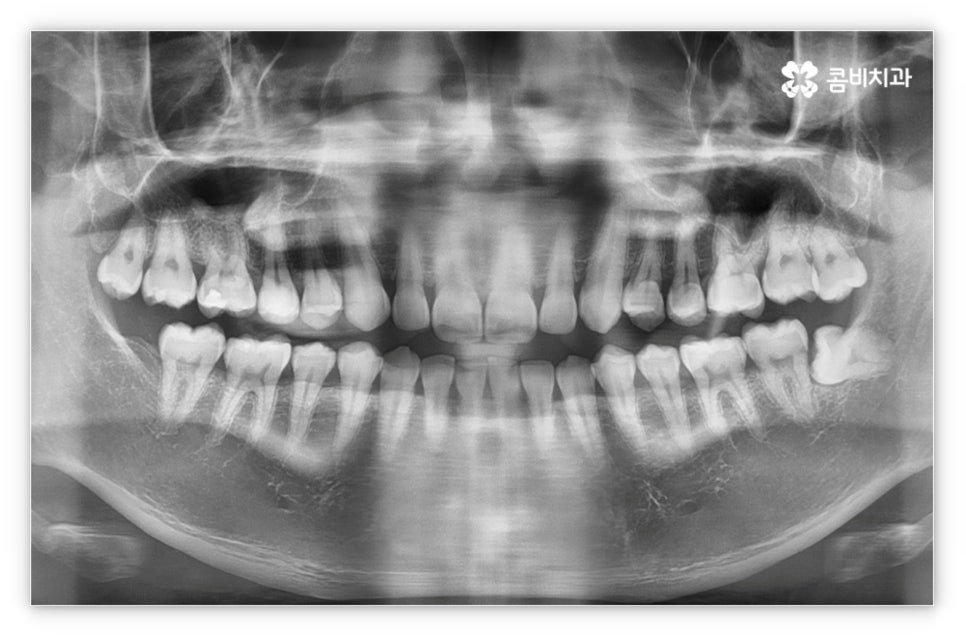

그리고 교정 치료는 그 목적상 위아래 교합이 똑바로 맞아 저작 기능을 제대로 수행할 수 있도록 하면서 가지런한 치열을 통해 발란스를 잡아주고 심미적으로도 좀 더 보기 좋은 안모를 형성하도록 하는 과정이기 때문에 환자의 치열과 교합, 얼굴 형태, 턱 관절 및 골격 구조 등 모든 부분을 세밀하게 파악하고 종합적으로 고려하여 각자에게 딱 맞는 교정 플랜을 세울 수 있도록 3D CT 와 같은 정밀 검진 기계를 갖추고 있는 치과에서 치료 받으시길 권유드리고 있는데요. 3D CT 는 일반 CT와 다르게 다각도에서 촬영을 하므로 환자분의 치아 위치, 턱관절, 얼굴의 정면 및 측면 등 다양한 정보를 수집하여 의료진 분들의 세밀한 파악을 돕는다는 장점이 있어요.

살펴본 바와 같이 앞니설측교정 의 장점에도 불구하고 아랫니 부분은 장치가 혀에 닿게 되기 때문에 환자분들께서 불편함을 느낄 수 있고 혹시라도 혀가 브라켓에 잘못 쓸리거나 눌렸을 때 통증이 발생할 수도 있으며 발음이 불분명해지는 문제가 생길 수 있는데요. 이러한 이유로 앞니설측교정 에 대해서 고민이 되시는 분들은 윗니 부분은 설측으로, 아랫니 부분은 일반 교정처럼 순측으로 진행하는 콤비 교정에 대해서 알아보시면 좋을 거예요. 위의 사진에서 살펴보실 수 있는 경우가 바로 이렇게 콤비 교정으로 진행한 환자분의 케이스인데 아랫니의 경우 보통 입술에 가려 별로 드러나지 않는 데다가 치아 색상인 세라믹 재질로 된 브라켓을 이용하기 때문에 설측 교정과 비교해도 심미성이 크게 떨어지지 않는다는 것을 알 수 있어요. 콤비 교정의 경우 설측 교정보다 비용적인 부담도 줄일 수 있으니 각 장치에 대한 장단점을 의료진분들과 충분히 상담하셔서 자신에게 맞는 장치를 선택하시면 좋을 거예요.